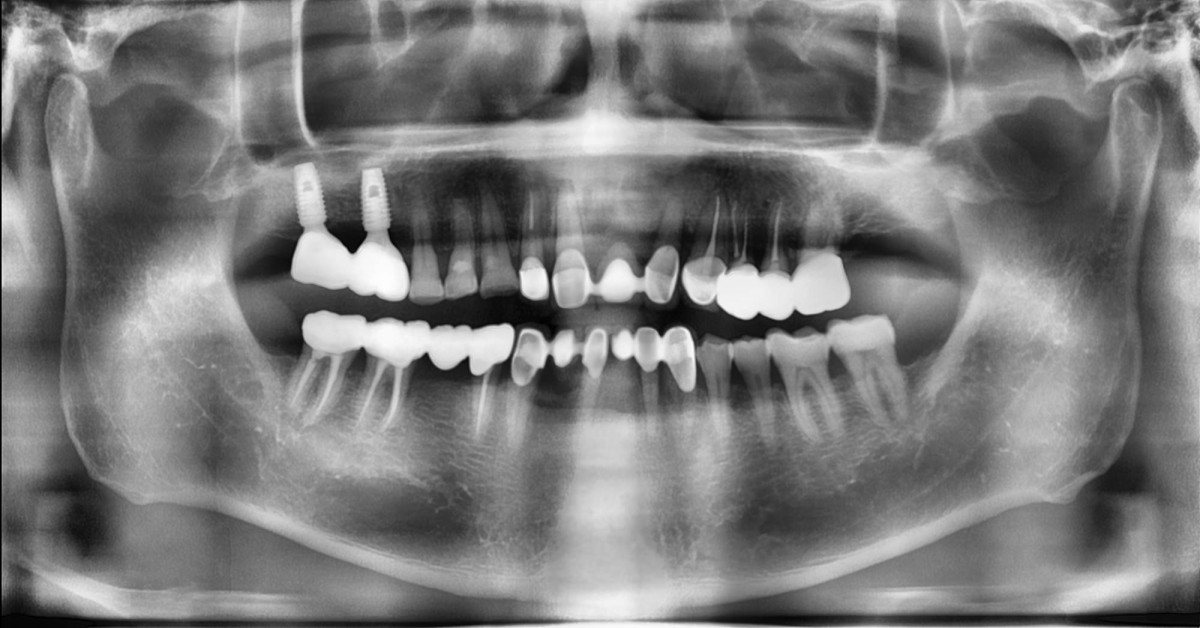

Socket Lift and Implant Placement in the right maxilla.

<GCacg> A 56-year-old male patient complained of pain in the right upper and lower jaws. And he wanted the upper first molar to be pulled out first.